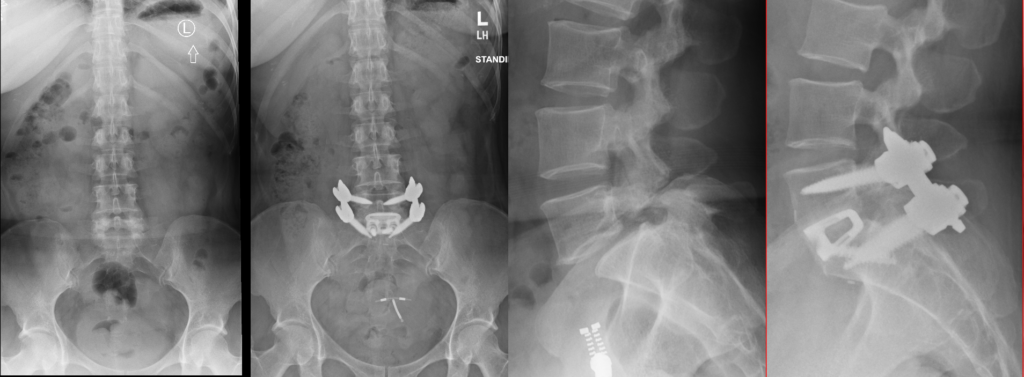

Anterior Lumbar Interbody Fusion